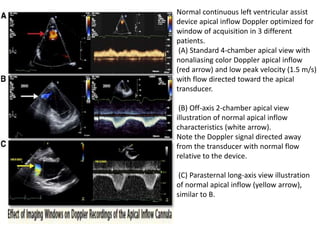

• Horton et al. demonstrated that the inflow

cannula can be imaged from the apical views

in 96% and the outflow conduit from the right

parasternal view in 98% of transthoracic

echos.

• For pulsatile LVADs, peak apical inflow

velocities are usually below 2.5 m/s with a

peak outflow cannula velocity 2 m/s.

• In comparison, continuous-flow LVADs have

normal, consistently phasic, slightly pulsatile,

low-velocity inflow and outflow patterns, with

peak velocities 2.0 m/s and typically 1.5 m/s.

• Normal apical inflow appears as nonturbulent

flow toward the apical transthoracic transducer.

• However, with off-axis imaging, the apparent

direction of normal flow relative to the

transducer may vary.

Normal continuous left ventricular assist

device apical inflow Doppler optimized for

window of acquisition in 3 different

patients.

(A) Standard 4-chamber apical view with

nonaliasing color Doppler apical inflow

(red arrow) and low peak velocity (1.5 m/s)

with flow directed toward the apical

transducer.

(B) Off-axis 2-chamber apical view

illustration of normal apical inflow

characteristics (white arrow).

Note the Doppler signal directed away

from the transducer with normal flow

relative to the device.

(C) Parasternal long-axis view illustration

of normal apical inflow (yellow arrow),

similar to B.